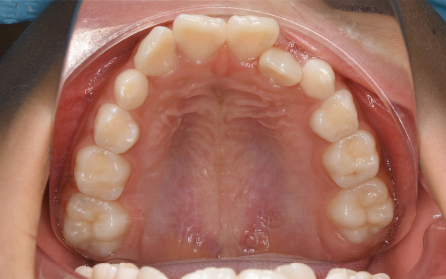

19歳 女性

主訴 「前歯のでこぼこを治したい」

診断 「両側側切歯のクロスバイトを伴う叢生症例」

上下前歯部の叢生の改善のため、歯と歯の間を0.5mm程度削ってスペースを確保しながら歯を並べました。患者さんの協力(マウスピースの使用状況等)も良好で、前歯が前方に突出することなく側切歯(2番目の歯)のクロスバイトも改善されました。前歯が突出しないように治療計画をたてないと口唇が閉じにくくなったり、口元がもっこりしてしまいます。治療期間は18か月でしたが、動的治療後は歯を安定させるために保定装置の使用が必要です(最低2年)。矯正治療では患者さんの協力が非常に重要であり(特にマウスピース矯正の場合は使用時間)、治療結果や治療期間に影響します。また、歯の移動にはワイヤー矯正、マウスピース矯正にかかわらず歯根吸収、歯肉退縮、歯髄壊死のリスクがあります。